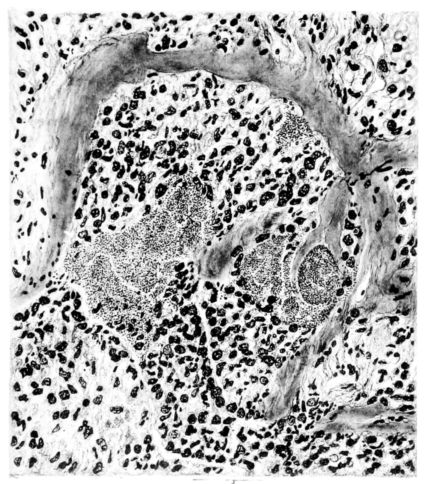

FIG. IV. AUTOPSY NO. 205. CONGESTION AND EDEMA OF THE SUBMUCOSA AND REGENERATION OF THE TRACHEAL EPITHELIUM.

The changes are less marked, perhaps, in the trachea than in its finer ramifications. The mucosa is constantly more or less destroyed and large areas, usually focal, are entirely devoid of their epithelial covering. This is replaced by a sparse exudate, composed largely of red blood cells, mucus, a small amount of fibrin, and nuclear fragments (Fig. II). It may dip into the submucosa for a short distance, but usually these indentures are associated with the ducts of the mucous glands into which the inflammatory reaction extends. A more striking feature than the exudate, however, is the edema and the congestion of the submucosa. The loose areolar tissue of the submucosa is spread widely apart, and throughout it distended blood vessels are very conspicuous. Occasionally such a vessel is broken and actual hemorrhage appears in the submucosa. Occasionally, too, the inflammation extends down the duct to the mucous gland itself, and here, also, aplastic inflammatory reaction is evident, inasmuch as the acini now stain intensely red with the cells undifferentiated from each other and specked here and there by broken remains of the dead nuclei (Fig. III). After the disease has continued for a short period, even at the end of five or six days, some regeneration of the epithelial lining may be seen (3) (Fig. IV). But despite this, the acute picture persists, and there goes on, side by side, an attempted repair characterized by epithelial regeneration and the same evidence of acute change. Since the lesion is essentially a superficial one, scars or contractures of any extent are not encountered in the trachea, even in examples of the disease that have ended fatally only after many weeks.[4]